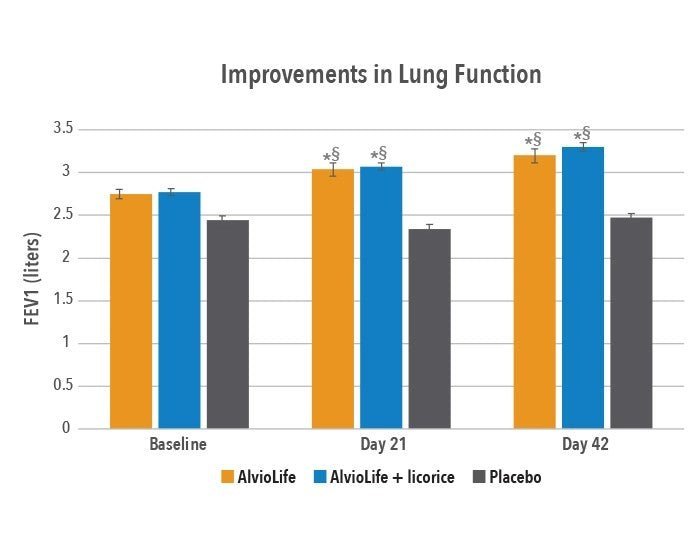

Etude clinique sur AlvioLife® pour le confort respiratoire – Revue internationale des sciences médicales (2021)

Évaluation de l’extrait combiné Boswellia-Aegle sur la fonction pulmonaire (VEMS/FVC) – Journal respiratoire clinique (2020)